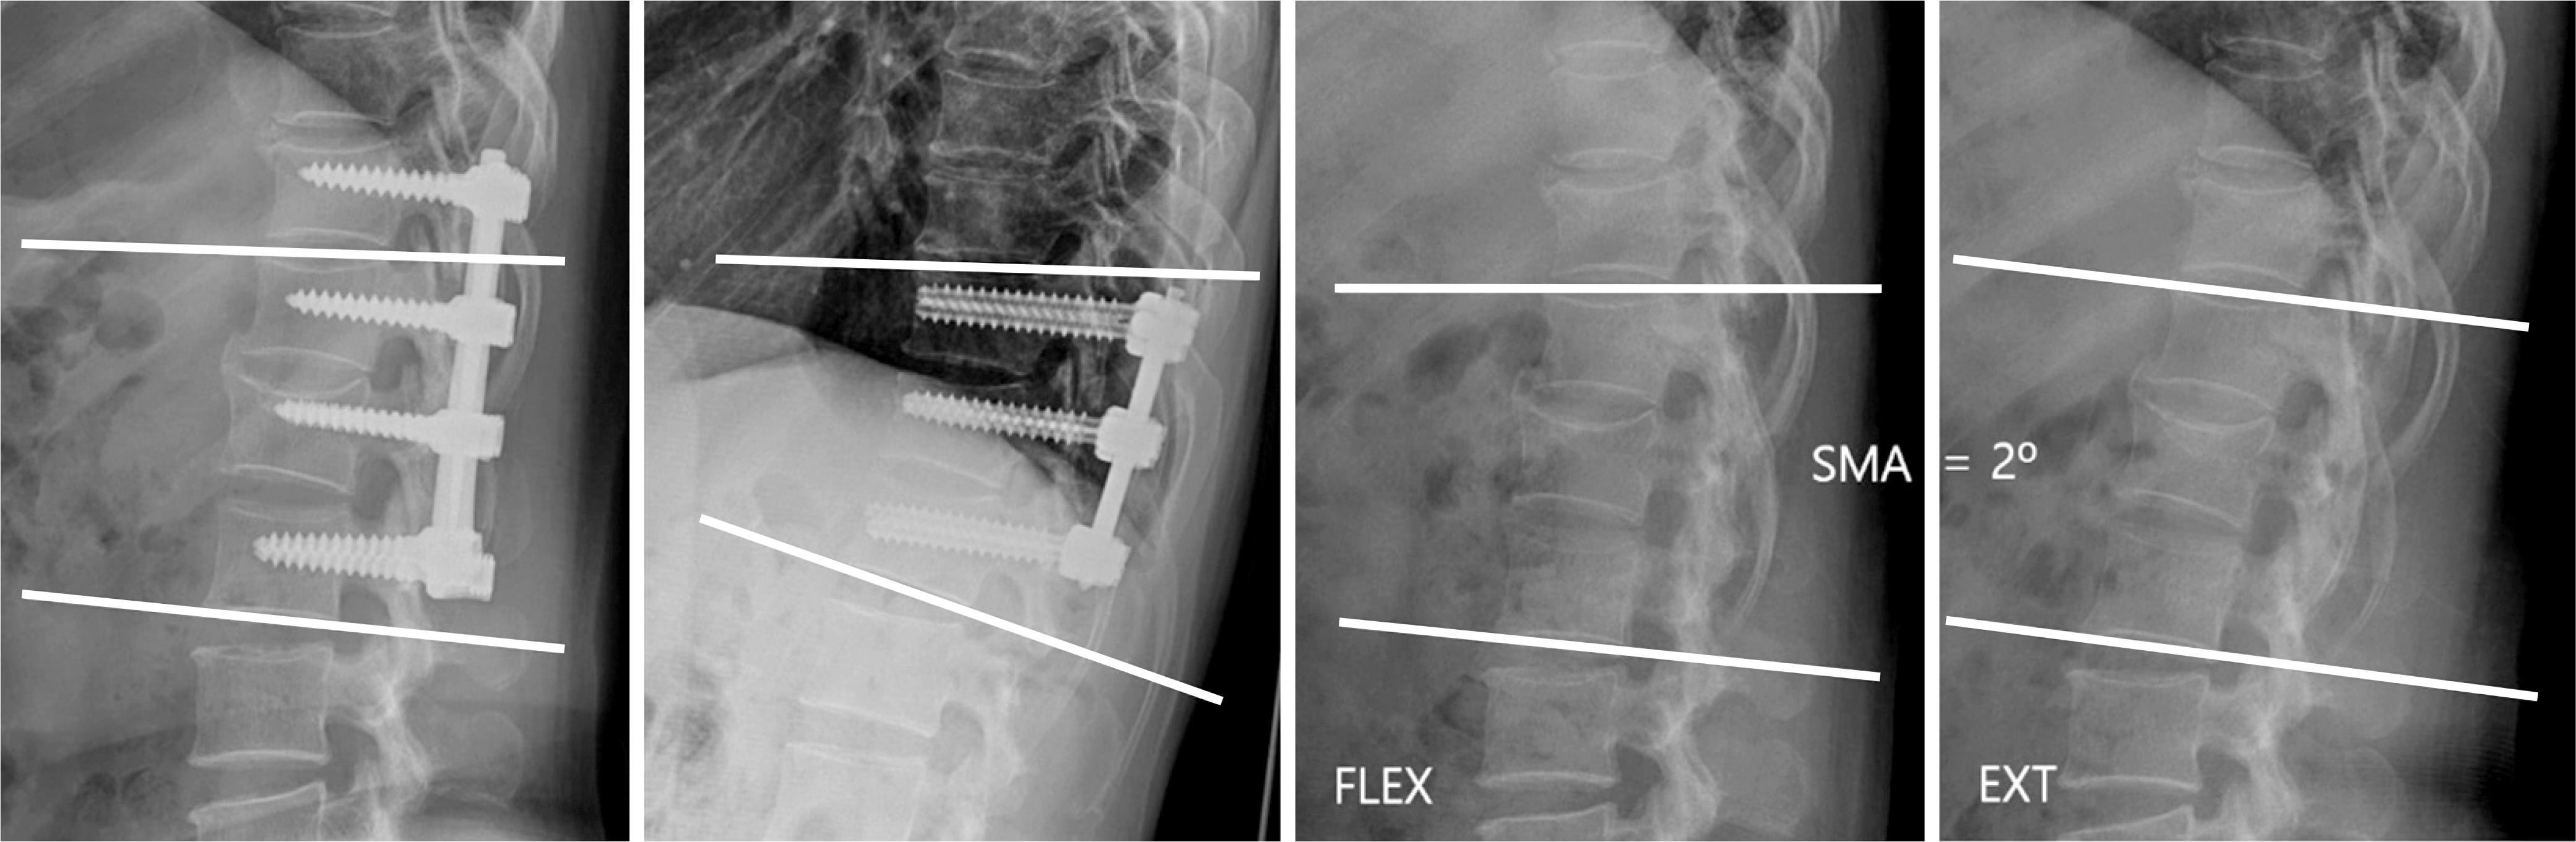

Fig. 2.

The segmental motion angle (SMA) was calculated as the difference between the local kyphotic angle on the flexion (FLEX) and extension (EXT) plain radiograph.

Segmental motion angle (°) 1.7±1.2 5.9±3.2 <0.001